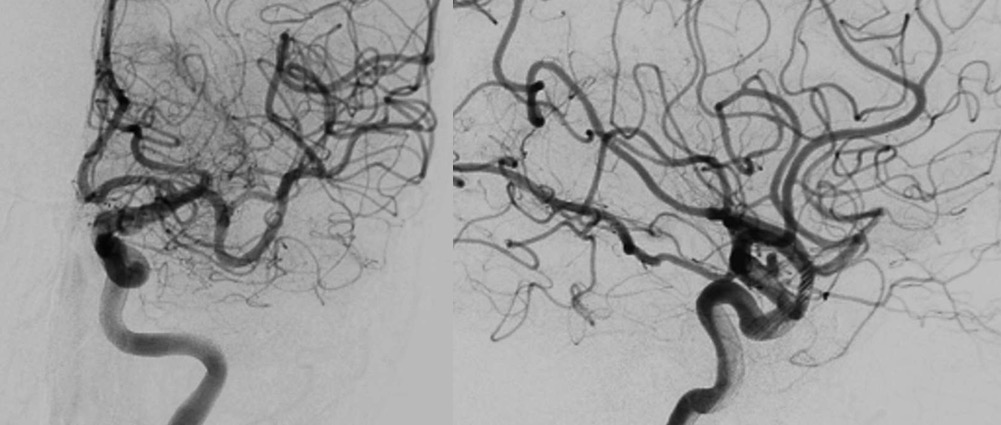

图5 造影显示动脉瘤瘤腔内造影剂滞留明显,载瘤动脉通畅

全麻满意后,常规消毒铺巾,采用改良 Seldinger技术穿刺右侧股动脉成功,置入6F动脉鞘。150 cm超滑泥鳅导丝带领5F单弯造影管分别行左侧椎动脉、双侧颈总动脉正侧位造影及双侧颈内动脉三维旋转造影,结果显示:左侧颈内动脉C6段动脉瘤;右侧颈内动脉C6段多发动脉瘤。向患者家属交代病情,考虑左侧颈内动脉C6段动脉瘤瘤体较大,且形态不规则,遂行左侧颈内动脉C6段动脉瘤密网支架置入术。150 cm超滑泥鳅导丝携 6F ENVOY DA导引导管达左侧颈内动脉C2段,Synchro-14微导丝携T-track支架微导管进入左侧大脑中动脉M1段,调整管头位置满意,管腔接高压肝素生理盐水持续滴注。经 T-track微导管送入Tubridge 4.5 mmx20 mm支架一枚,调整位置满意后精准释放,完全覆盖动脉瘤,即刻造影显示支架打开良好,贴壁良好,动脉瘤瘤腔内造影剂滞留明显,载瘤动脉通畅。遂结束手术。

1. 该患者为双侧颈内动脉多发动脉瘤,合并高血压等危险因素,右侧颈内动脉可见多发小动脉瘤,左侧颈内动脉动脉瘤瘤体较大,不规则,破裂风险较高,这是我们选择左侧颈内动脉动脉瘤介入治疗的指征。